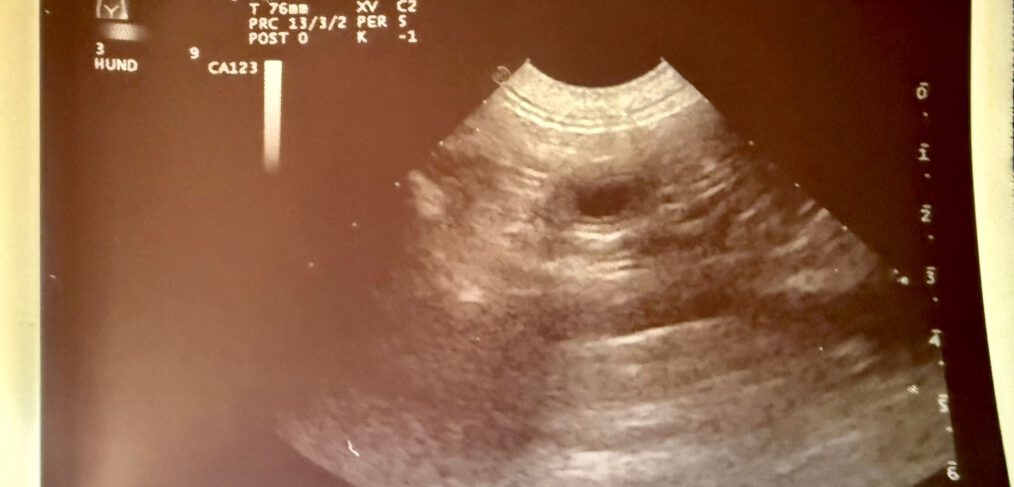

Kornay Hunting MATILDA wurde am 03.Mai von ALBIN Pondcastle of Alpine Girls gedeckt und die Trächtigkeit vom weltbesten Tierärzteteam PRAXIS KREUZBERGL bestätigt! Wir erwarten die Ankunft unseres V2 Wurfes Anfang Juli . Alle 18 Welpen von Gale und Prim sind bereits vergeben !